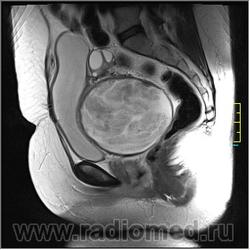

Госсипибома, или текстилома - это название группы осложнений после хирургических вмешательств в результате оставленных в теле пациента инородных предметов. Термин "Госсипибома" состоит из латинского слова gossypium (хлопок) и слова из языка суахили boma (место, где что-то спрятано), по другим данным - греческого "oma" - частицы, обозначающей опухоль. Так или иначе, госсипибома представляет собой матрикс из хлопка, окруженный гранулемой инородного тела. Термин текстилома появился позже и стал использоваться вместо термина "госсипибома", когда в хирургии вместо хлопка начали применять синтетические материалы.

Ж, 35 лет. Состояние после субтотальной гистерэктомии без придатков по поводу осложненных родов около полугода назад. Обратилась на МРТ в связи с болями и неприятными ощущениями в области малого таза.

Вот такая картинка.